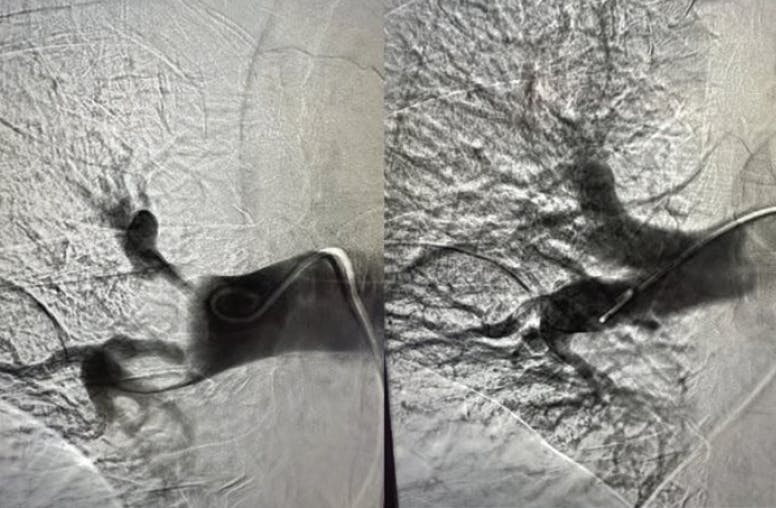

A 16-F, 33-cm Gore DrySeal sheath (Gore & Associates) was advanced into the vasculature and placed in the inferior vena cava. The Lightning Flash catheter was then tracked into the right PA until proximal to the initial embolic segment. Aspiration was initiated, and the catheter was advanced into the clot burden. Clot detection mode immediately activated, indicated by the system’s flashing yellow LED light. The thrombus was ingested in a single pass that took under 1 minute. After reaching a satisfactory result in the right PA, focus was shifted to the left PA. The Penumbra 6-F Select™ Catheter was advanced over a 0.035-inch guidewire to track the Lightning Flash catheter easily to the left PA. The same procedural aspiration steps were repeated, and a large amount of thrombus was removed and observed in the Penumbra ENGINE canister (Figure 1).

Figure 1. Thrombus removed from the PA.

Angiography showed exceptional improvement from the initial images taken prior to intervention (Figure 2 and Figure 3). The patient’s mean PA pressure dropped by 23% on the table. It is also notable that the final result was accomplished in only 15 minutes of device time with 250 mL of blood loss, exemplifying the efficiency of the Lightning Flash thrombectomy system.

Figure 2. Pre- and postthrombectomy angiogram of the left PA.

Figure 3. Pre- and postthrombectomy angiogram of the right PA.